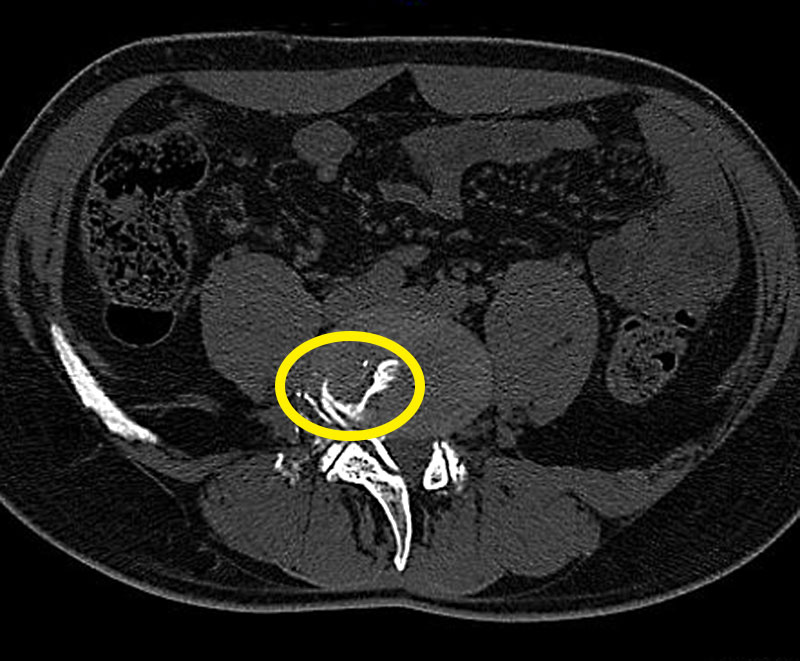

もう1つは、Modic変性で、椎間板などの慢性的なストレスや疲労が原因と考えられます。これまではボルトを入れて固定するしかありませんでしたが、内視鏡で内部をクリーニングすることで、7-8割の患者さんの痛みがとれることがわかってきました。これらの手術も、ヘルニアと同様すべて局所麻酔で数日の入院期間で行うことができます。

Modic変性(慢性的なストレスや疲労が原因)